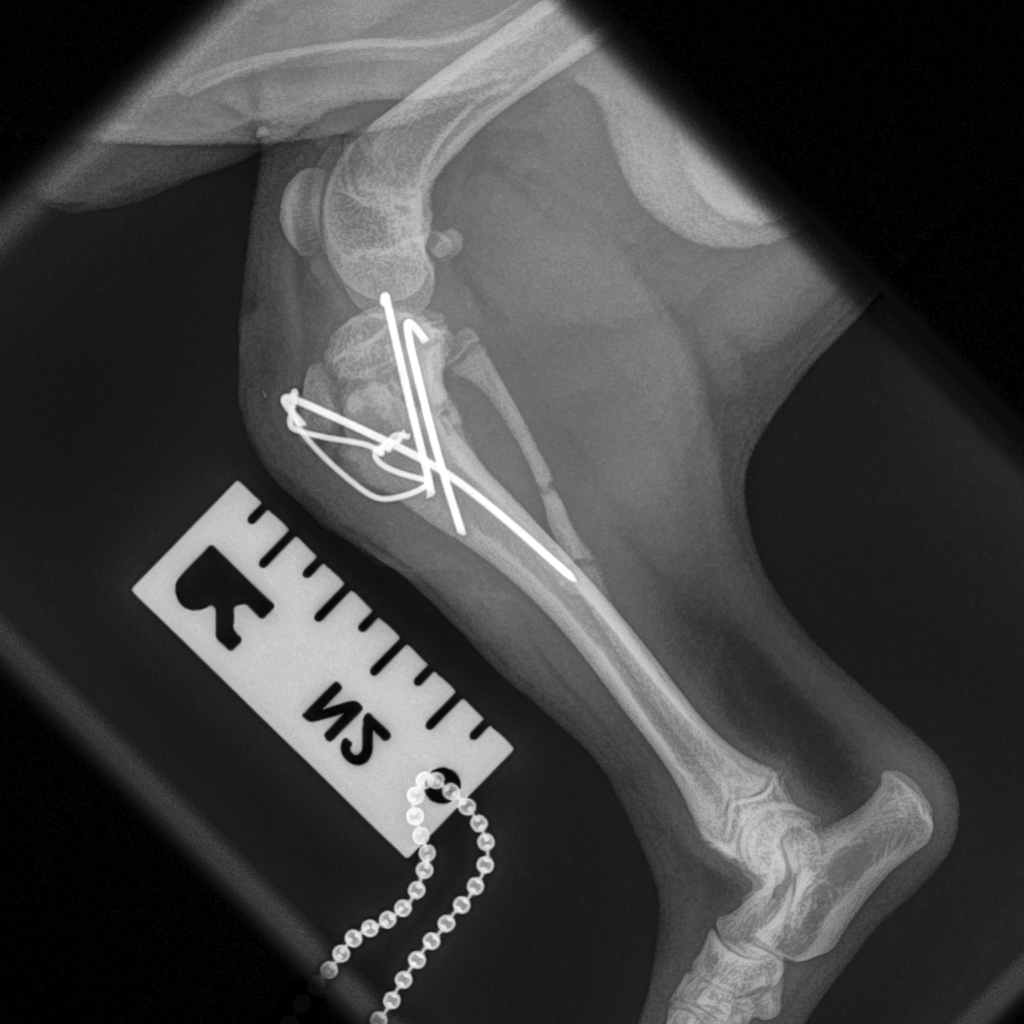

Fractures can be treated in various ways but most long-bone fractures in dogs and cats are best treated with surgery. Internal fixation is often the preferred method and may involve the use of pins and wires, or plates and screws.

At Movement Referrals, we have a range of implant systems which gives us a broad range of options to fix the full range of possible fractures in dogs and cats. Some specific examples include the Feline Lateral Ilial Plate (FLIP; Fusion Implants) and the Lateral Epicondylar Anatomical Pate (LEAP, Fusion Implants).